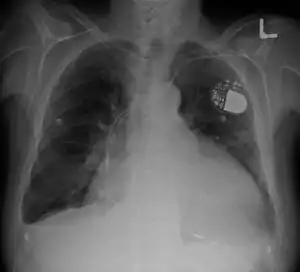

| Cardiomegaly on chest X-ray with a pacemaker | |

- Pacemaker: Coordinates contractions between ventricles. In people at risk of arrhythmias, drug therapy or an implantable cardioverter-defibrillator (ICD).